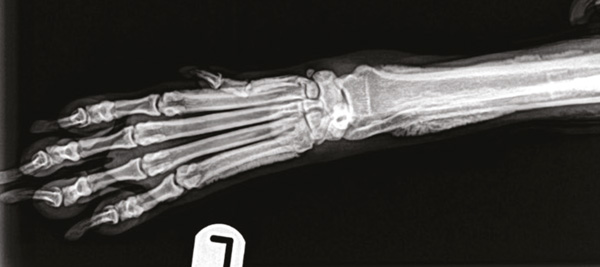

Figure 3: Dorsopalmar view of the left distal forelimb. The new periosteal bone is sharply marginated with distinct edges: its shape is irregular, almost palisading. As a result of the new bone deposition, there also appears to be increased opacity in the medullary cavity of these bones.

Ideally, a three-view thoracic and two-view abdominal radiologic study should always be part of the diagnostic database when screening for this disease.11 Radiographic bony changes (which may not be immediately evident in the early stages of disease) consist of a polyostotic, bilaterally symmetrical periosteal proliferation at the diaphysis of distal long bones, with subsequent progression to more proximal bones.11 This proliferation is often described as ‘palisading’, as periosteum deposition occurs at right angles to the long axis of the bone. It usually starts on the distal abaxial surface of bones10 and it appears to be ‘scalloped'. It is important to note that this condition always spares the joint spaces.3 Over time, the new bone deposed becomes rounder and smoother and it begins to be laid down in parallel layers with the bone cortex. Occasionally, new bone can get deposed in the soft tissues and be completely isolated from the bone cortex.7

Radiographs highlighted a lung mass, along with a polyostotic, ‘palisading’ periosteal proliferation in all four distal limbs.